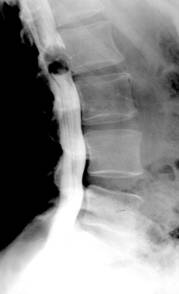

Modificarile radiologice ale spondilodiscitei tuberculoase sunt:

foarte mici focare osteolitice in apropierea discului, adesea invizibile radiografic;

diminuarea inaltimii spatiului discal ce antreneaza modificari de ax ale coloanei vertebrale (cifoza sau scoliaza);

stergerea suprafetelor discale si structura neomogena a corpurilor vertebrale adiacente discului, cu zone de osteoliza imprecis delimitate; localizarea leziunilor distructive fata-n fata pe cele doua platouri vertebrale implicate realizeaza asa zisa imagine “in oglinda”;

deformarea si reducerea, uneori extrema, a inaltimii corpilor vertebrali cu modificari de ax ale coloanei (cifoza pottica), dislocari, luxatii;

abcesul rece (pottic) apare ca o opacitate uni sau bilaterala ce proemina lateral, omogena, bine delimitata, depasind apofizele transverse. Abcesele din regiunea toracala medie nu migreaza la distanta si stagneaza in spatiul costovertebral sau intercostal, putand eroda coastele. Abcesele toracolombare coboara uneori pe teaca psoasilor in regiunea lombara, astfel ca vor modifica (bomba) umbra psoasului. Abcesele din regiunea cervicala deplaseaza anterior traheea si esofagul;

modificari reconstructive sub forma liniilor de demarcatie, zone de ingrosare a structurii osoase ce delimiteaza leziunea si fac sa reapara conturul vertebral care se recalcifica;

tardiv apar punti osoase intervertebrale ce demonstreaza fuziunea dintre vertebre;

evolutia fara tratament duce la distrugeri importante ale corpurilor vertebrale, aparitia sechestrelor si mari modificari de statica.